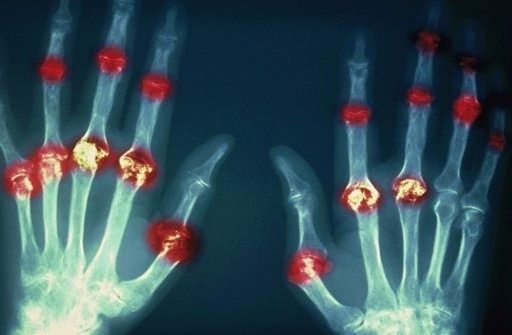

?類風(fēng)濕關(guān)節(jié)炎

類風(fēng)濕關(guān)節(jié)炎是一種高度致殘的自身免疫性疾病,發(fā)病十年的患者中至少有50%的人失去勞動能力。

類風(fēng)濕關(guān)節(jié)炎©Health Same of Flickr

1977年,Baldwin在用骨髓干細胞移植治療再生障礙性貧血的過程中,意外發(fā)現(xiàn)患者的類風(fēng)濕關(guān)節(jié)炎得到緩解。

2004年,歐洲骨髓移植和抗風(fēng)濕病聯(lián)盟對60例類風(fēng)濕病關(guān)節(jié)炎移植患者進行回顧性分析,這些患者的關(guān)節(jié)破壞都達到不可修復(fù)程度,生活不能自理,通過干細胞移植治療后,67%的患者得到明顯緩解。

我國國內(nèi)多家醫(yī)院已開展了干細胞治療類風(fēng)濕性關(guān)節(jié)炎的臨床研究。首例自體干細胞移植治療類風(fēng)濕關(guān)節(jié)炎在北京協(xié)和醫(yī)院完成。經(jīng)過5個月隨訪,這些經(jīng)常規(guī)藥物治療失敗且病情發(fā)展迅速的患者,在接受干細胞移植治療后,癥狀均獲得改善,關(guān)節(jié)腫脹消失,各項檢查指標恢復(fù)正常。

解放軍323醫(yī)院2011年的一項臨床研究中,27位患者(對照組)只使用藥物治療;另外153位患者(細胞治療組)在藥物治療的基礎(chǔ)上進行臍帶間充質(zhì)干細胞輸注。結(jié)果顯示,治療組DAS28、HAQ 評分、ACR20較對照組下降明顯(分值越低,療效越好),Th1/Th2趨于平衡、Treg升高與臨床實驗指標及癥狀的緩解直接相關(guān)。